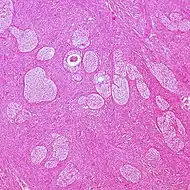

| Dysgerminoma of ovary[13] | 1% of all ovarian cancers[13] | ![]() | ||||